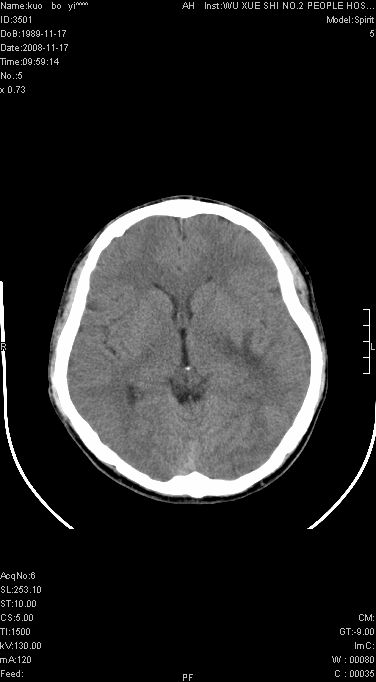

右侧肢体无力一周

这么大片面积,中线居中,占位效应不明显,考虑脑梗塞。

灶中央有厚环状高密度成分,顶叶皮质局部有显著的受压表现,多支持占位性病变,胶质瘤?淋巴瘤?转移?不知患者年龄多大,病史较短,不除外炎性

左顶叶较大范围水肿区,内见明显强化的片状 棉絮状组织,但占位效应不明显。多考虑:脑炎!

不像脑梗死,低密度区中心,有一密度增高边界清楚的,近脑组织密度的病灶.建议进一步强化及肺和肝等重要脏器检查.